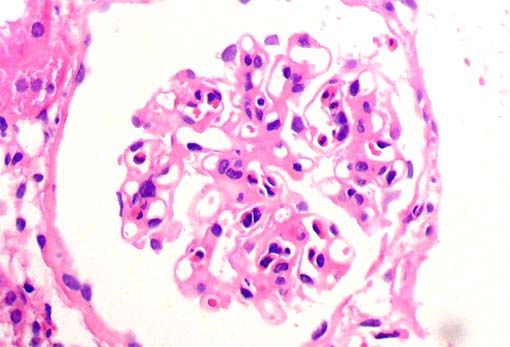

Figura 1.

H&E, X100.